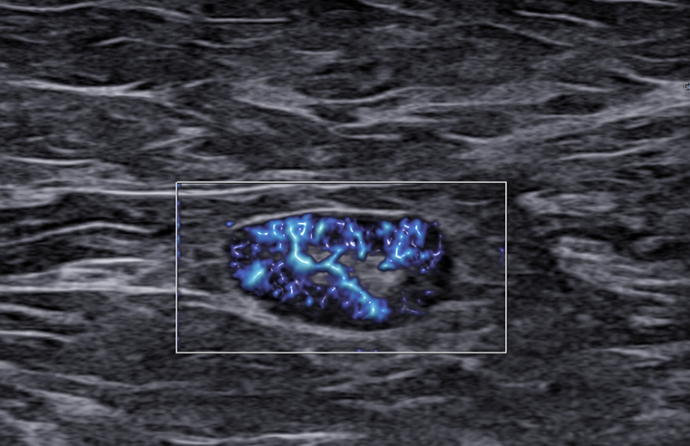

Rak piersi a obraz węzłów chłonnych. LN-RADS - część 2

Dr n. med. Paweł Guzik

Ultrasonografia jest jedną z czterech głównych metod w diagnostyce chorób piersi. Współczesna sytuacja epidemiologiczna, czyli ciągły wzrost zachorowań na raka piersi u kobiet, wymaga od nas dyskusji na ten temat.